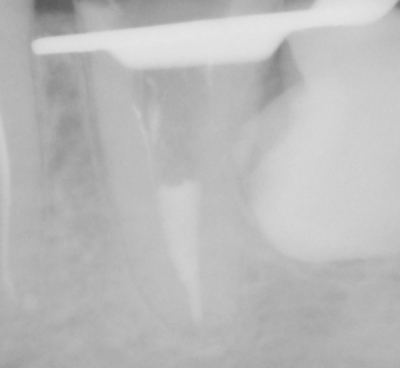

PRZYKŁADY LECZENIA KANAŁOWEGO WYKONANEGO PRZEZ NASZ ZESPÓŁ

Przykłady odstępstw anatomicznych kanałów zębowych